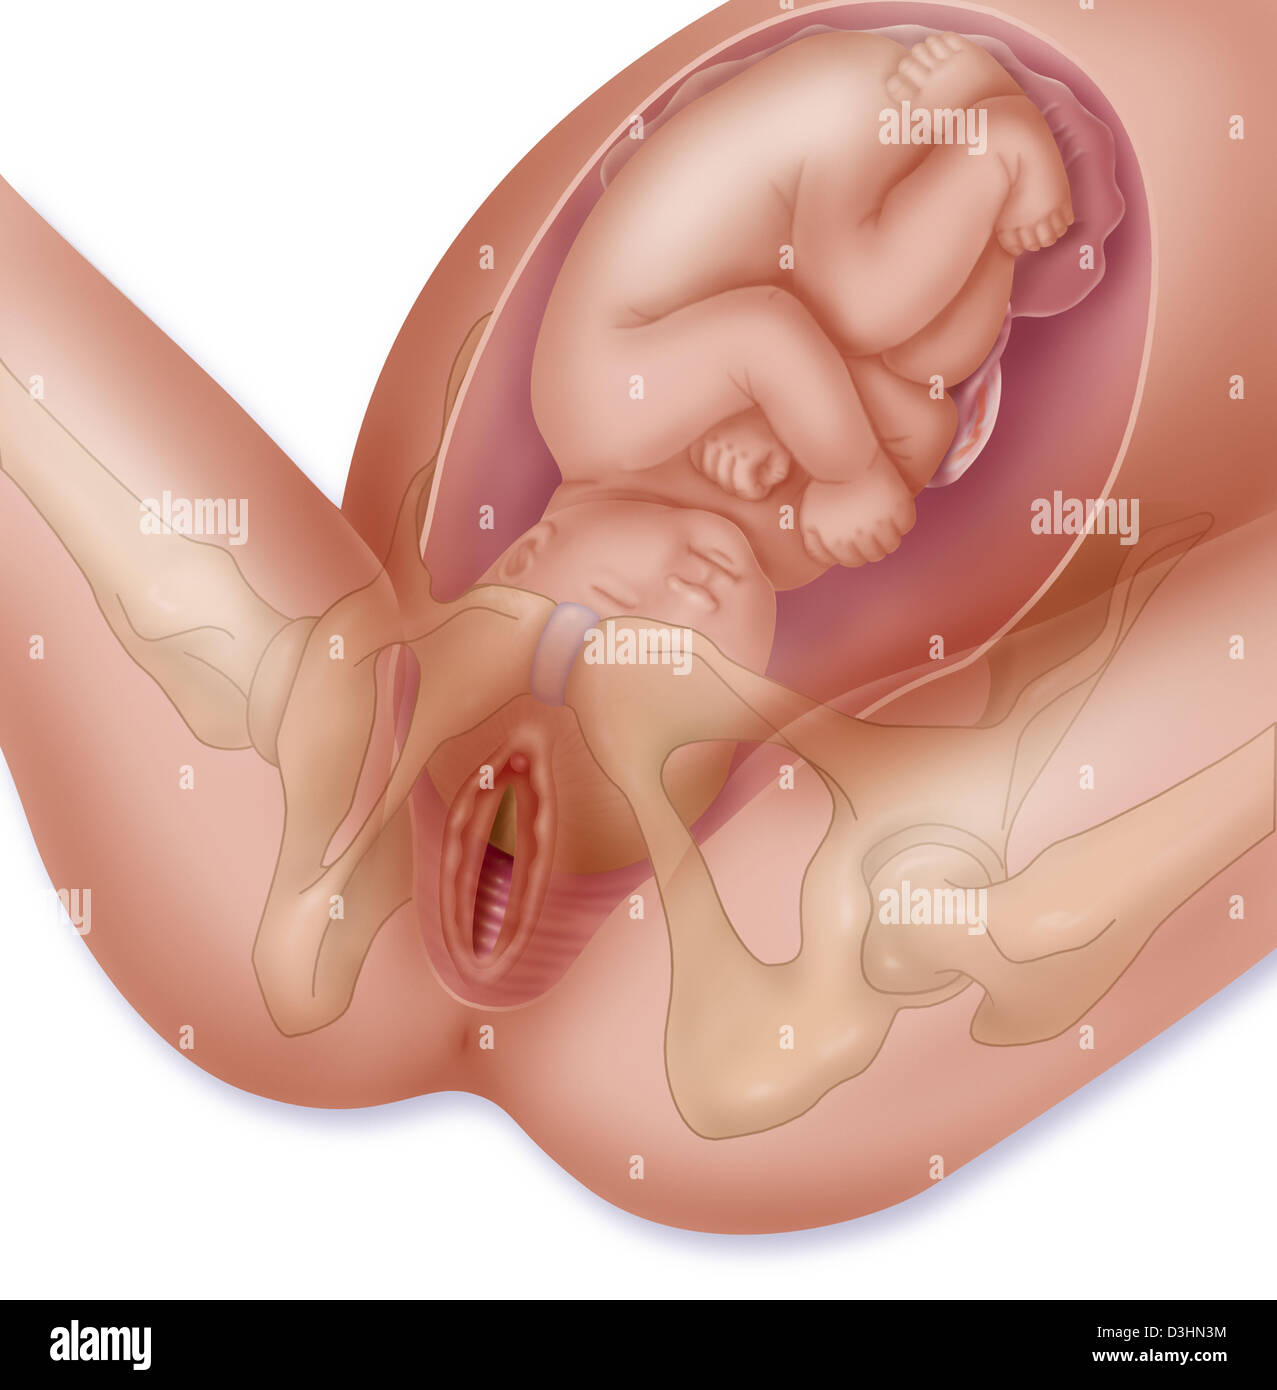

Fetus Positions in Uterus, Illustration Stock Photohttps://www.alamy.com/image-license-details/?v=1https://www.alamy.com/fetus-positions-in-uterus-illustration-image353173031.html

Fetus Positions in Uterus, Illustration Stock Photohttps://www.alamy.com/image-license-details/?v=1https://www.alamy.com/fetus-positions-in-uterus-illustration-image353173031.htmlRF2BEGBPF–Fetus Positions in Uterus, Illustration

Childbirth, stage 1: the baby is engaged in the pelvis. Stock Photohttps://www.alamy.com/image-license-details/?v=1https://www.alamy.com/childbirth-stage-1-the-baby-is-engaged-in-the-pelvis-image476926081.html

Childbirth, stage 1: the baby is engaged in the pelvis. Stock Photohttps://www.alamy.com/image-license-details/?v=1https://www.alamy.com/childbirth-stage-1-the-baby-is-engaged-in-the-pelvis-image476926081.htmlRF2JKWT29–Childbirth, stage 1: the baby is engaged in the pelvis.